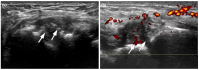

The degree of BE and synovial hyperplasia in SNRA or SPRA is more serious, and the blood flow signal is more abundant. However, the degree of synovial hyperplasia in osteoarthritis was mild, and no obvious blood flow signal was detected (Figures 1, 2, 3 and 4). Magnetic resonance imaging (MRI) studies of SPRA also showed serious BE (Figure 5).

One of the limitations to this study is the lack of other imaging and pathological comparisons. Magnetic resonance imaging is an effective tool to examine early RA and to evaluate therapeutic effect; it is considered gold standard for RA research. However, in practice, it is time-consuming to perform MRI examinations on all the affected joints of the patient's hands. Moreover, MRI can be costly for many patients. On the other hand, although needle biopsy of joint synovium is helpful for accurate diagnosis of disease, it is an invasive operation with high technical requirements for the operator and may, thus, not be the best choice for patients.